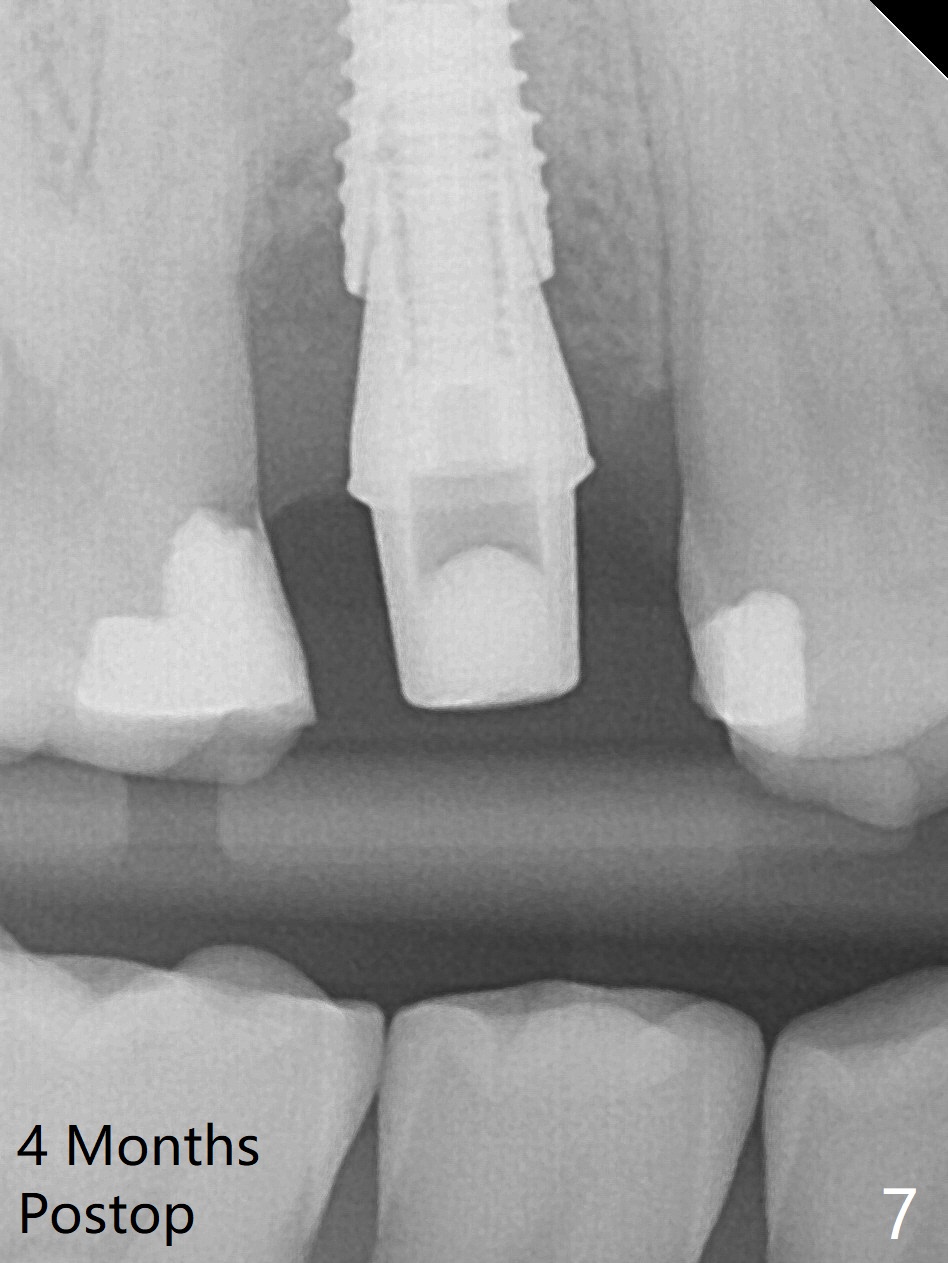

When the tooth #4 with vertical root fracture (Fig.1) is extracted, the buccal plate is found to be lost. The lowest point of the defect is shown as black dashed line in Fig.2 (yellow dashed line: sinus floor). After use of 2.5 mm reamer for 21 mm (buccal gingival level) and 3.0 mm reamer for ~17 mm, a 3.8x15 mm dummy implant is placed with 30 Ncm and 1.85 mm apical space (Fig.3 pink outline). A 3.8x18 mm (definitive) implant is placed with <40 Ncm with the implant plateau apical to the lingual crest (Fig.4,5). The buccal plate defect is repaired by Vanilla Graft (Fig.6 *) before and after insertion of a 4.5x4(3) mm abutment. The buccal plate defect seems to being repaired 4 months postop (Fig.7). Occlusal wear suggests bruxism, which is also associated with the root fracture. Night guard is recommended. The defect repair is close to completion 8 months post cementation (Fig.8). The crown/abutment is found to be loose 1 year 4 months post cementation and retightened without checking whether there is clinical 2nd DO caries of #3 (Fig.9, "sensitive to water pik"). A few days later, DO composite is being removed. It is difficult to determine whether the 2nd DO caries or gap has been removed with the neighboring crown in place. When the crown/abutment is removed and gingival retractions are inserted, there is no decay. The gap is removed. With Toflemire in place, the crown/abutment is reseated and hand tightened; after packable composite, the crown/abutment is removed, there is no more DO gap.